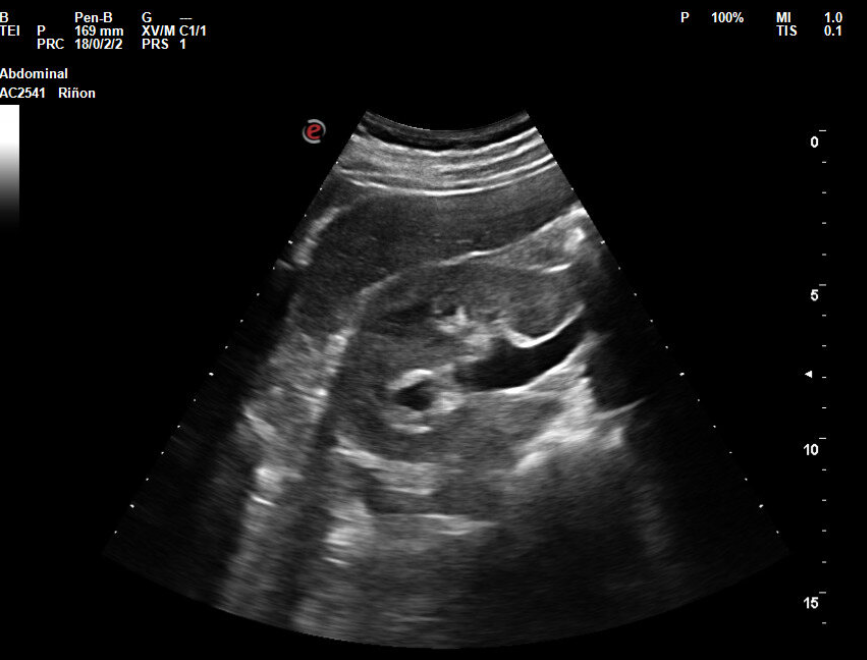

Hallazgos ecográficos

En la ecografía objetivamos discreta dilatación calicial y dilatación del uréter derecho. Se visualiza vejiga de características normales, con jet ureteral bilateral presente. No se objetivan litiasis. Tras explicar signos y síntomas de alarma por los que acudir a urgencias se decide solicitar estudio con ecografía preferente para revalorar y verificar resolución del cuadro, y realizar consulta preferente a urología.

Cólico renal derecho. Hidronefrosis leve. Las imágenes de ecografía obtenidas en el hospital son concordantes con las del centro de salud. También la actitud terapéutica elegida ya que se opta por una actitud conservadora a la espera de respuesta de urología.